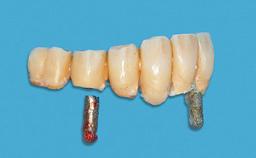

In 2007, a 97-year-old patient presented for treatment at the Geneva Dental School. His dentist had retired. Like many elderly patients, he was left without regular dental care. He lived on a geriatric ward, as he was partly dependent on help with most of the activities of daily living (ADL), such as getting dressed, washing, taking a shower, or climbing stairs. However, he was able to go to the bathroom and get up from bed on his own (ADL score 80, min. 18, max. 126; a low score signifies a high degree of dependency) (Lawton and Brody 1969). He was not bound to a wheelchair, but used a walker. Moreover, he was socially highly active—his family visited on a regular basis and he often went to the restaurant with his friend, who was some 20 years younger. His cognitive function did not seem to be impaired in a normal conversation, although his MMSE score was only 21/30 at that time (Folstein and coworkers 1975). The patient was a retired pharmacist, and his latest passion was astronomy.